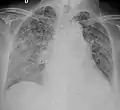

| Chest X ray showing miliary tuberculosis | |

Miliary tuberculosis is a form of tuberculosis that is characterized by a wide dissemination into the human body and by the tiny size of the lesions (1–5 mm). Its name comes from a distinctive pattern seen on a chest radiograph of many tiny spots distributed throughout the lung fields with the appearance similar to millet seeds—thus the term "miliary" tuberculosis. Miliary TB may infect any number of organs, including the lungs, liver, and spleen.[2] Miliary tuberculosis is present in about 2% of all reported cases of tuberculosis and accounts for up to 20% of all extra-pulmonary tuberculosis cases.[3]